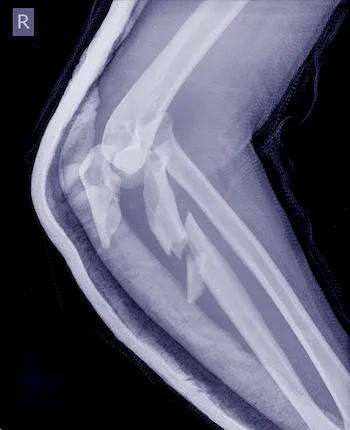

| ▸ | Röntgen Erkennung von Knochenbrüchen (zuverlässige Ergebnisse erst im späteren Krankheitsverlauf – neue, starke Rückenschmerzen; chronische Rückenschmerzen unbekannter Ursache; hohes Lebensalter; niedrige Knochendichte; mehrere, alte Brüche; Größenverlust von > 5 cm seit 25. Lebensjahr und > 2 cm bei Kontrolluntersuchungen) |

| ▸ | Computertomografie (CT), Magnetresonanztomografie (MRT) Erkennung von frischer oder verheilter Fraktur und genaue Auswertung der Frakturmorphologie |

Röntgenaufnahmen von verschiedenen Knochenbrüchen bei Osteoporose

Diese Diagnostikmethoden kombiniert sind von großer Bedeutung, um individuelle Risikoprofile zu erstellen und eine präzise Behandlung einzuleiten. Eine frühzeitige Untersuchung ermöglicht es Ihnen, gezielt Maßnahmen zu ergreifen und so die Stabilität Ihres Knochengerüsts langfristig zu sichern.